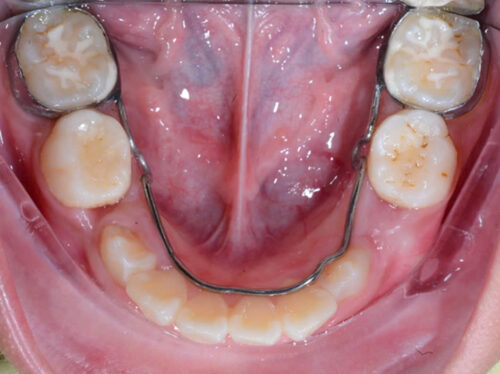

Hàm giữ khoảng khi mất răng 5 sữa, răng 6 đã mọc